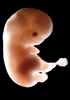

Carnegie Stage 20 (50 post-ovulatory days)

Most embryos at stage 20 are approximately 50-51 postovulatory days old and measure 21-23 mm in length. Distinguishing criteria for this stage include upper limbs slightly bent at the elbows, short stubby fingers, hands curving over the cardiac region but still far apart from each other, and a fringe-like vascular plexus that marks growth centers laterally in the superficial tissues of the head.